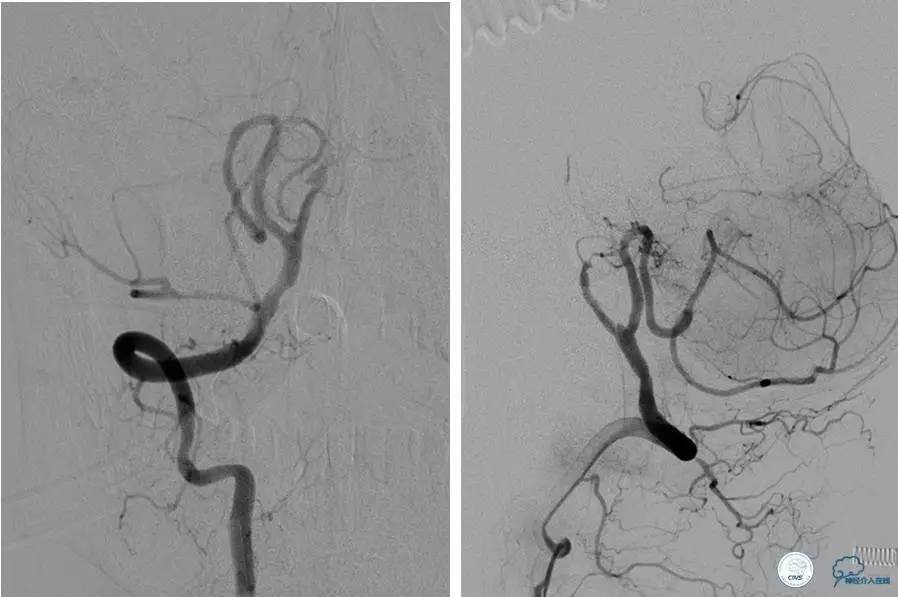

患者:77岁女性,住院后虽然给予药物治疗,仍再次卒中发作。

微导丝穿过狭窄时,有不安全感觉,不很顺畅,拐弯。

经反复尝试,微导丝仍顺利穿过闭塞段。

可见弥漫性长段硬化,选用合适球囊扩张后。

闭塞段很长且成角,置入Solitaire支架,效果好。